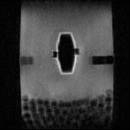

■PharmaSense の撮像例

試験用錠剤の水和化

投入直後 4時間後 7時間後

黒い部分は固形部,白い部分は水和によるゲル状部分を示す。

中央左右に黒く見えるのは錠剤のホルダー,下はガラスビーズ。